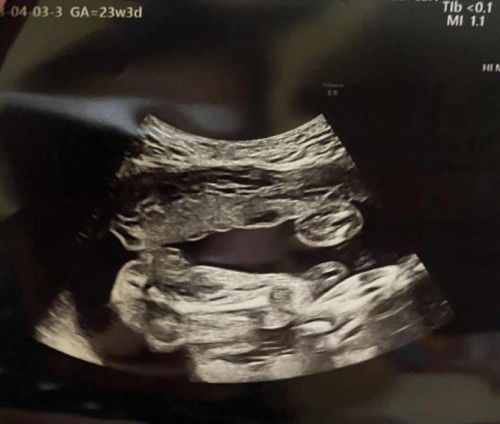

Is it a Boy or a Girl

Ano po sa tingin nyo? 23 weeks Appears Female daw po. Sure na po ba?🥰